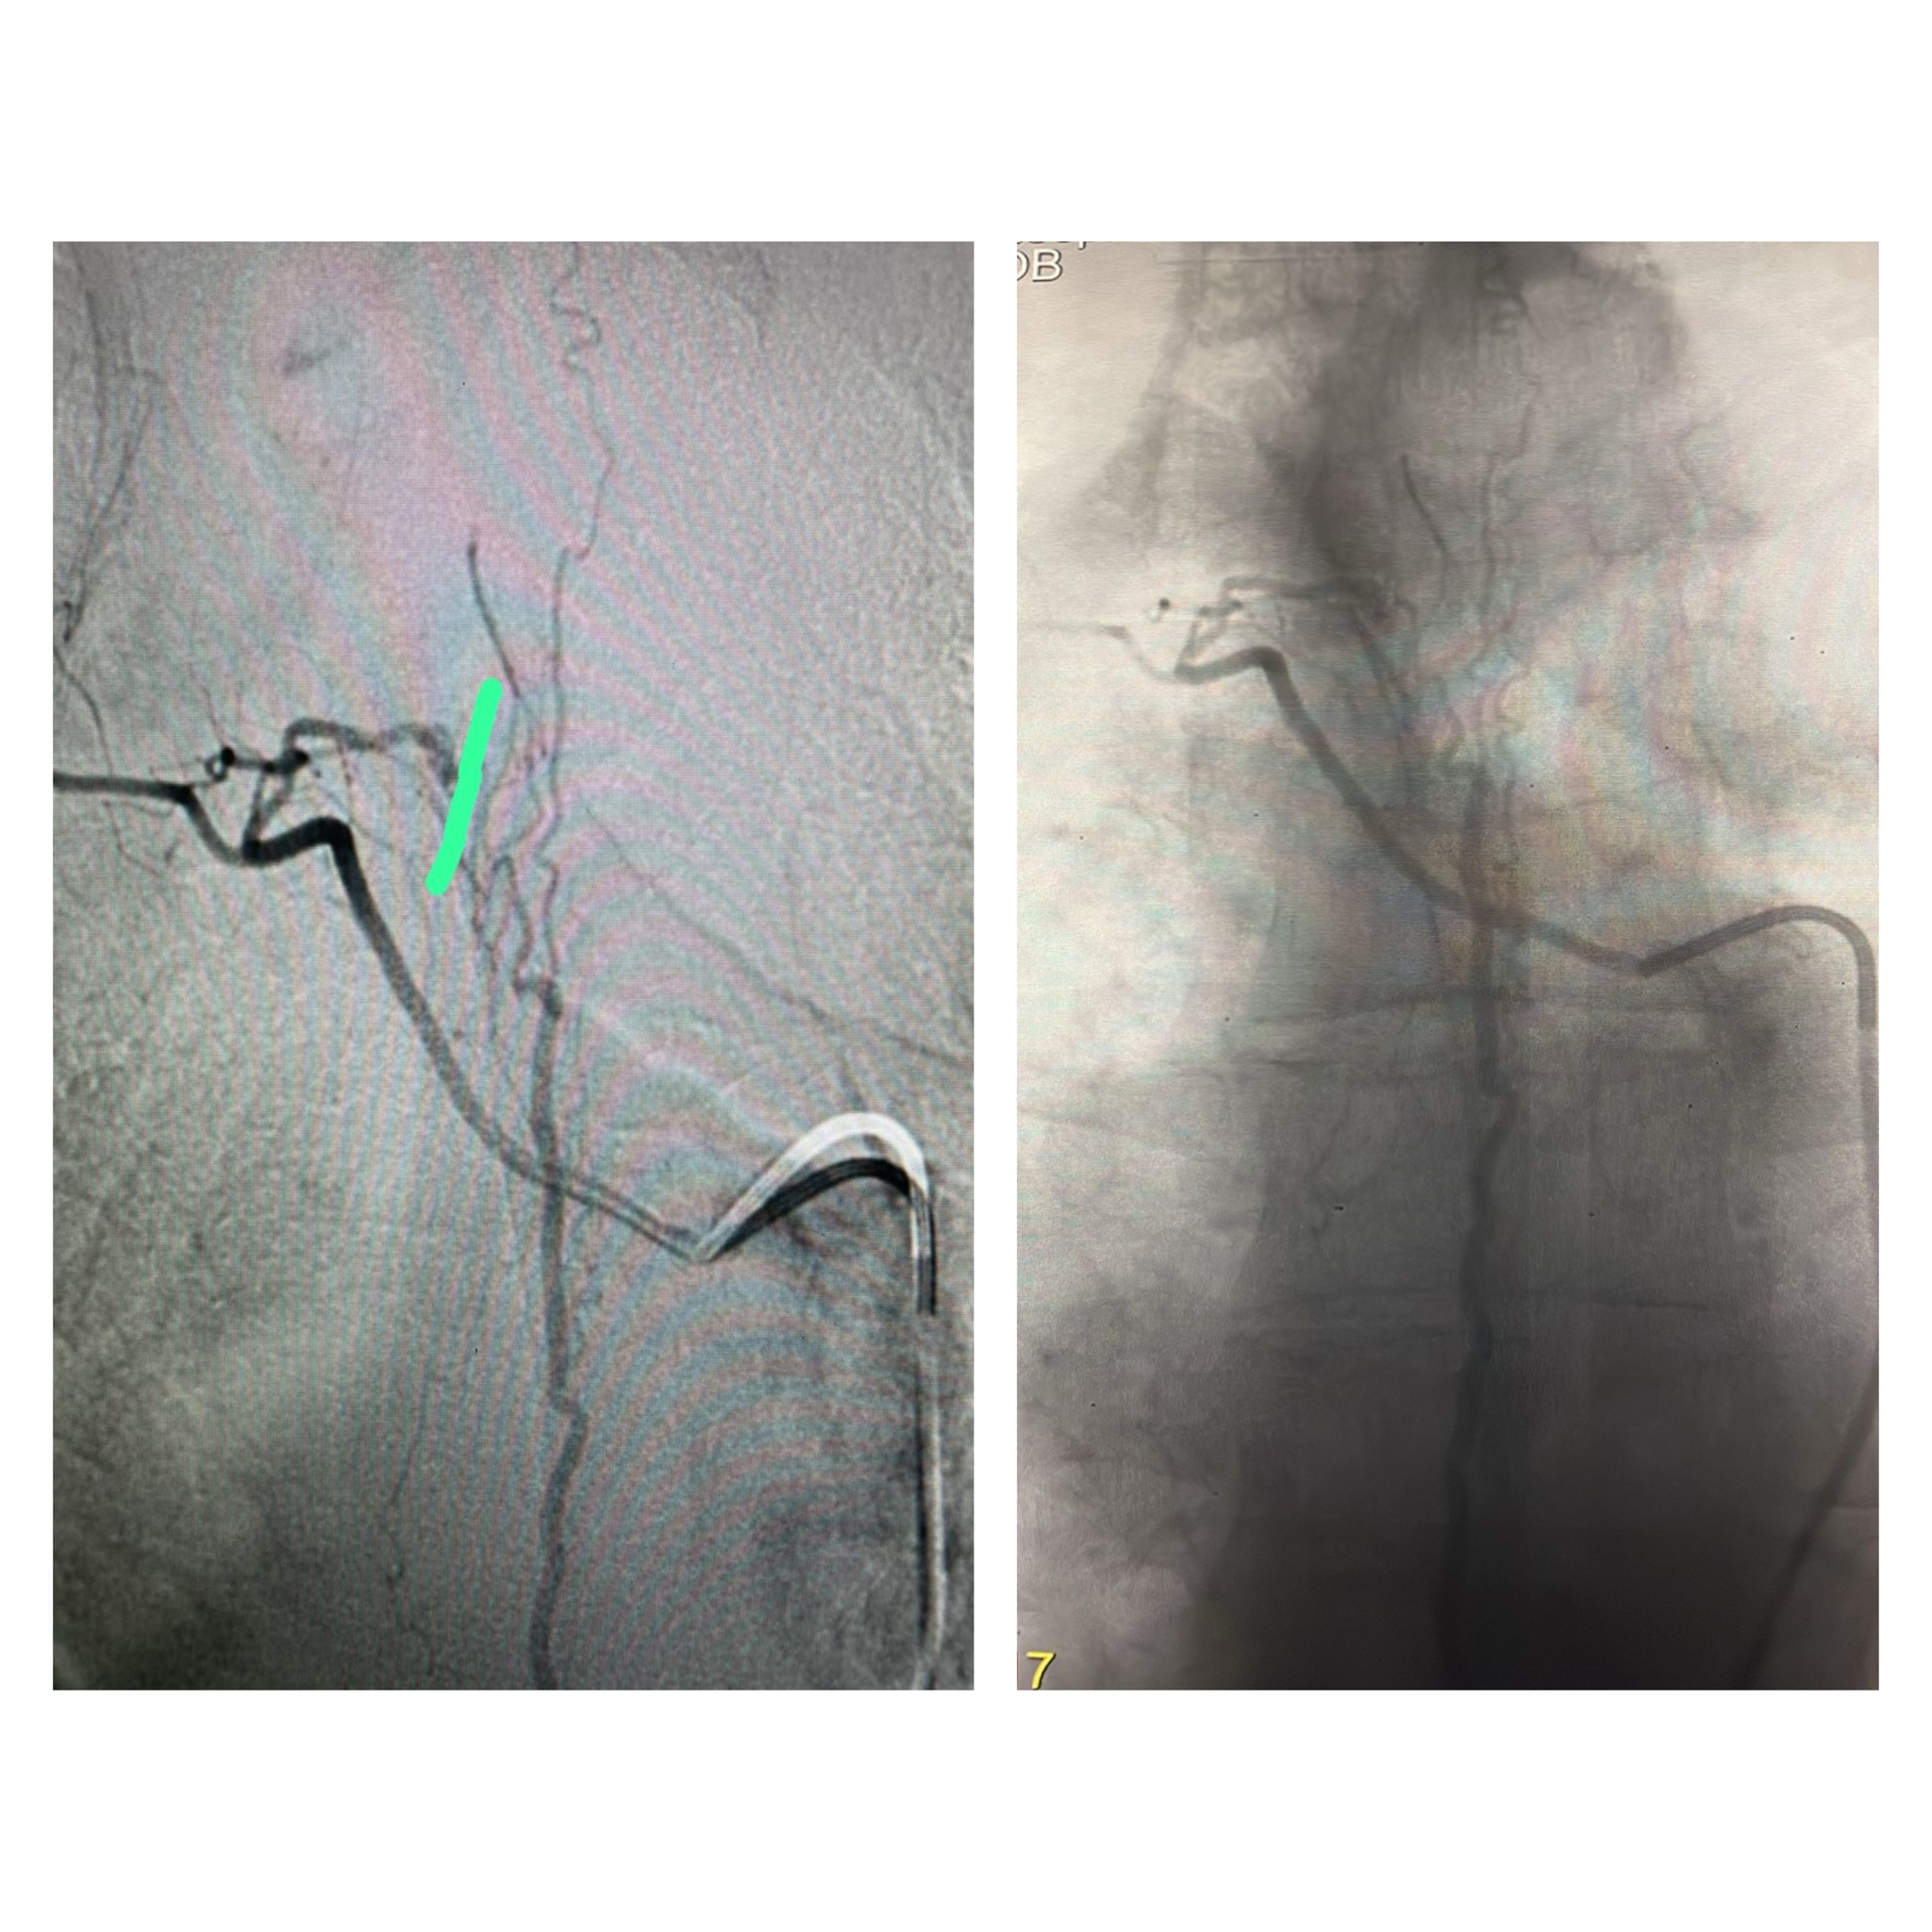

تمكّن الفريق الطبي في وحدة القسطرة بالمستشفى التخصصي، بقيادة الدكتور حازم حبوب استشاري الاشعة التداخلية، من إجراء تداخل طبي متقدم لمعالجة حالة شلل طرفي ناتج عن وجود تشوه شرياني وريدي في النخاع الشوكي، وذلك تحت المراقبة الفسيولوجية العصبية الدقيقة.

وتمت العملية بنجاح من خلال استحضار الإمكانيات الحسية والحركية للمريض أثناء الإجراء، لتفادي أي مضاعفات محتملة. وأسفرت العملية عن تحسن ملحوظ في حالة المريض، حيث أصبح قادراً على المشي بشكل أفضل وبمفرده، إضافة إلى استعادته السيطرة الكاملة على وظائف الجهاز الهضمي.

ويُعد هذا التدخل الأول من نوعه الذي يُنفذ في وحدة القسطرة بالمستشفى، مما يعكس التقدم المستمر في مستوى الرعاية الطبية والتخصصية المقدّمة.